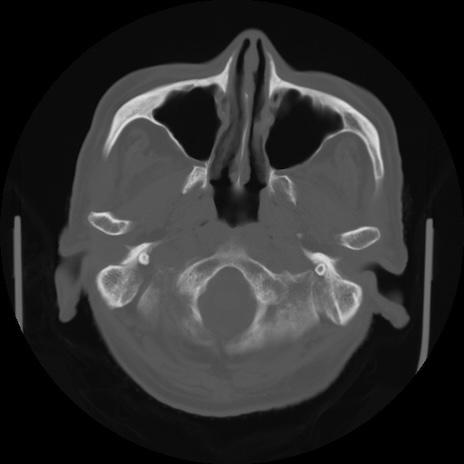

【頭部】症例5 CT(横断像)

【症例】80歳代 男性

【主訴】頭部打撲

【現病歴】外出先で椅子から立ち上がる際に、つまづいて後方へ転倒し受傷。転倒時に意識はあった。

【既往歴】高血圧、不整脈、アルツハイマー病

【身体所見】BP 217/71、HR 96、JCS1-1、 難聴あり、顔色良好、右後頭部に擦過創あり。神経学的異常なし。

症例5の画像所見と診断は?